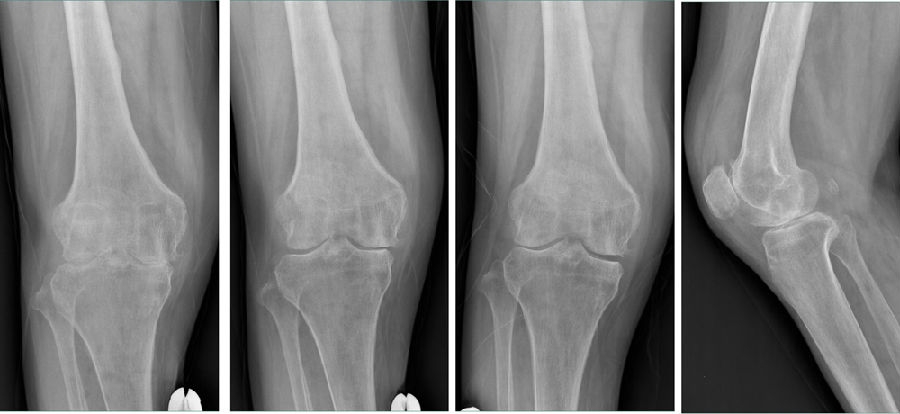

Case1:LUK治疗外侧间室OA

术前

术后